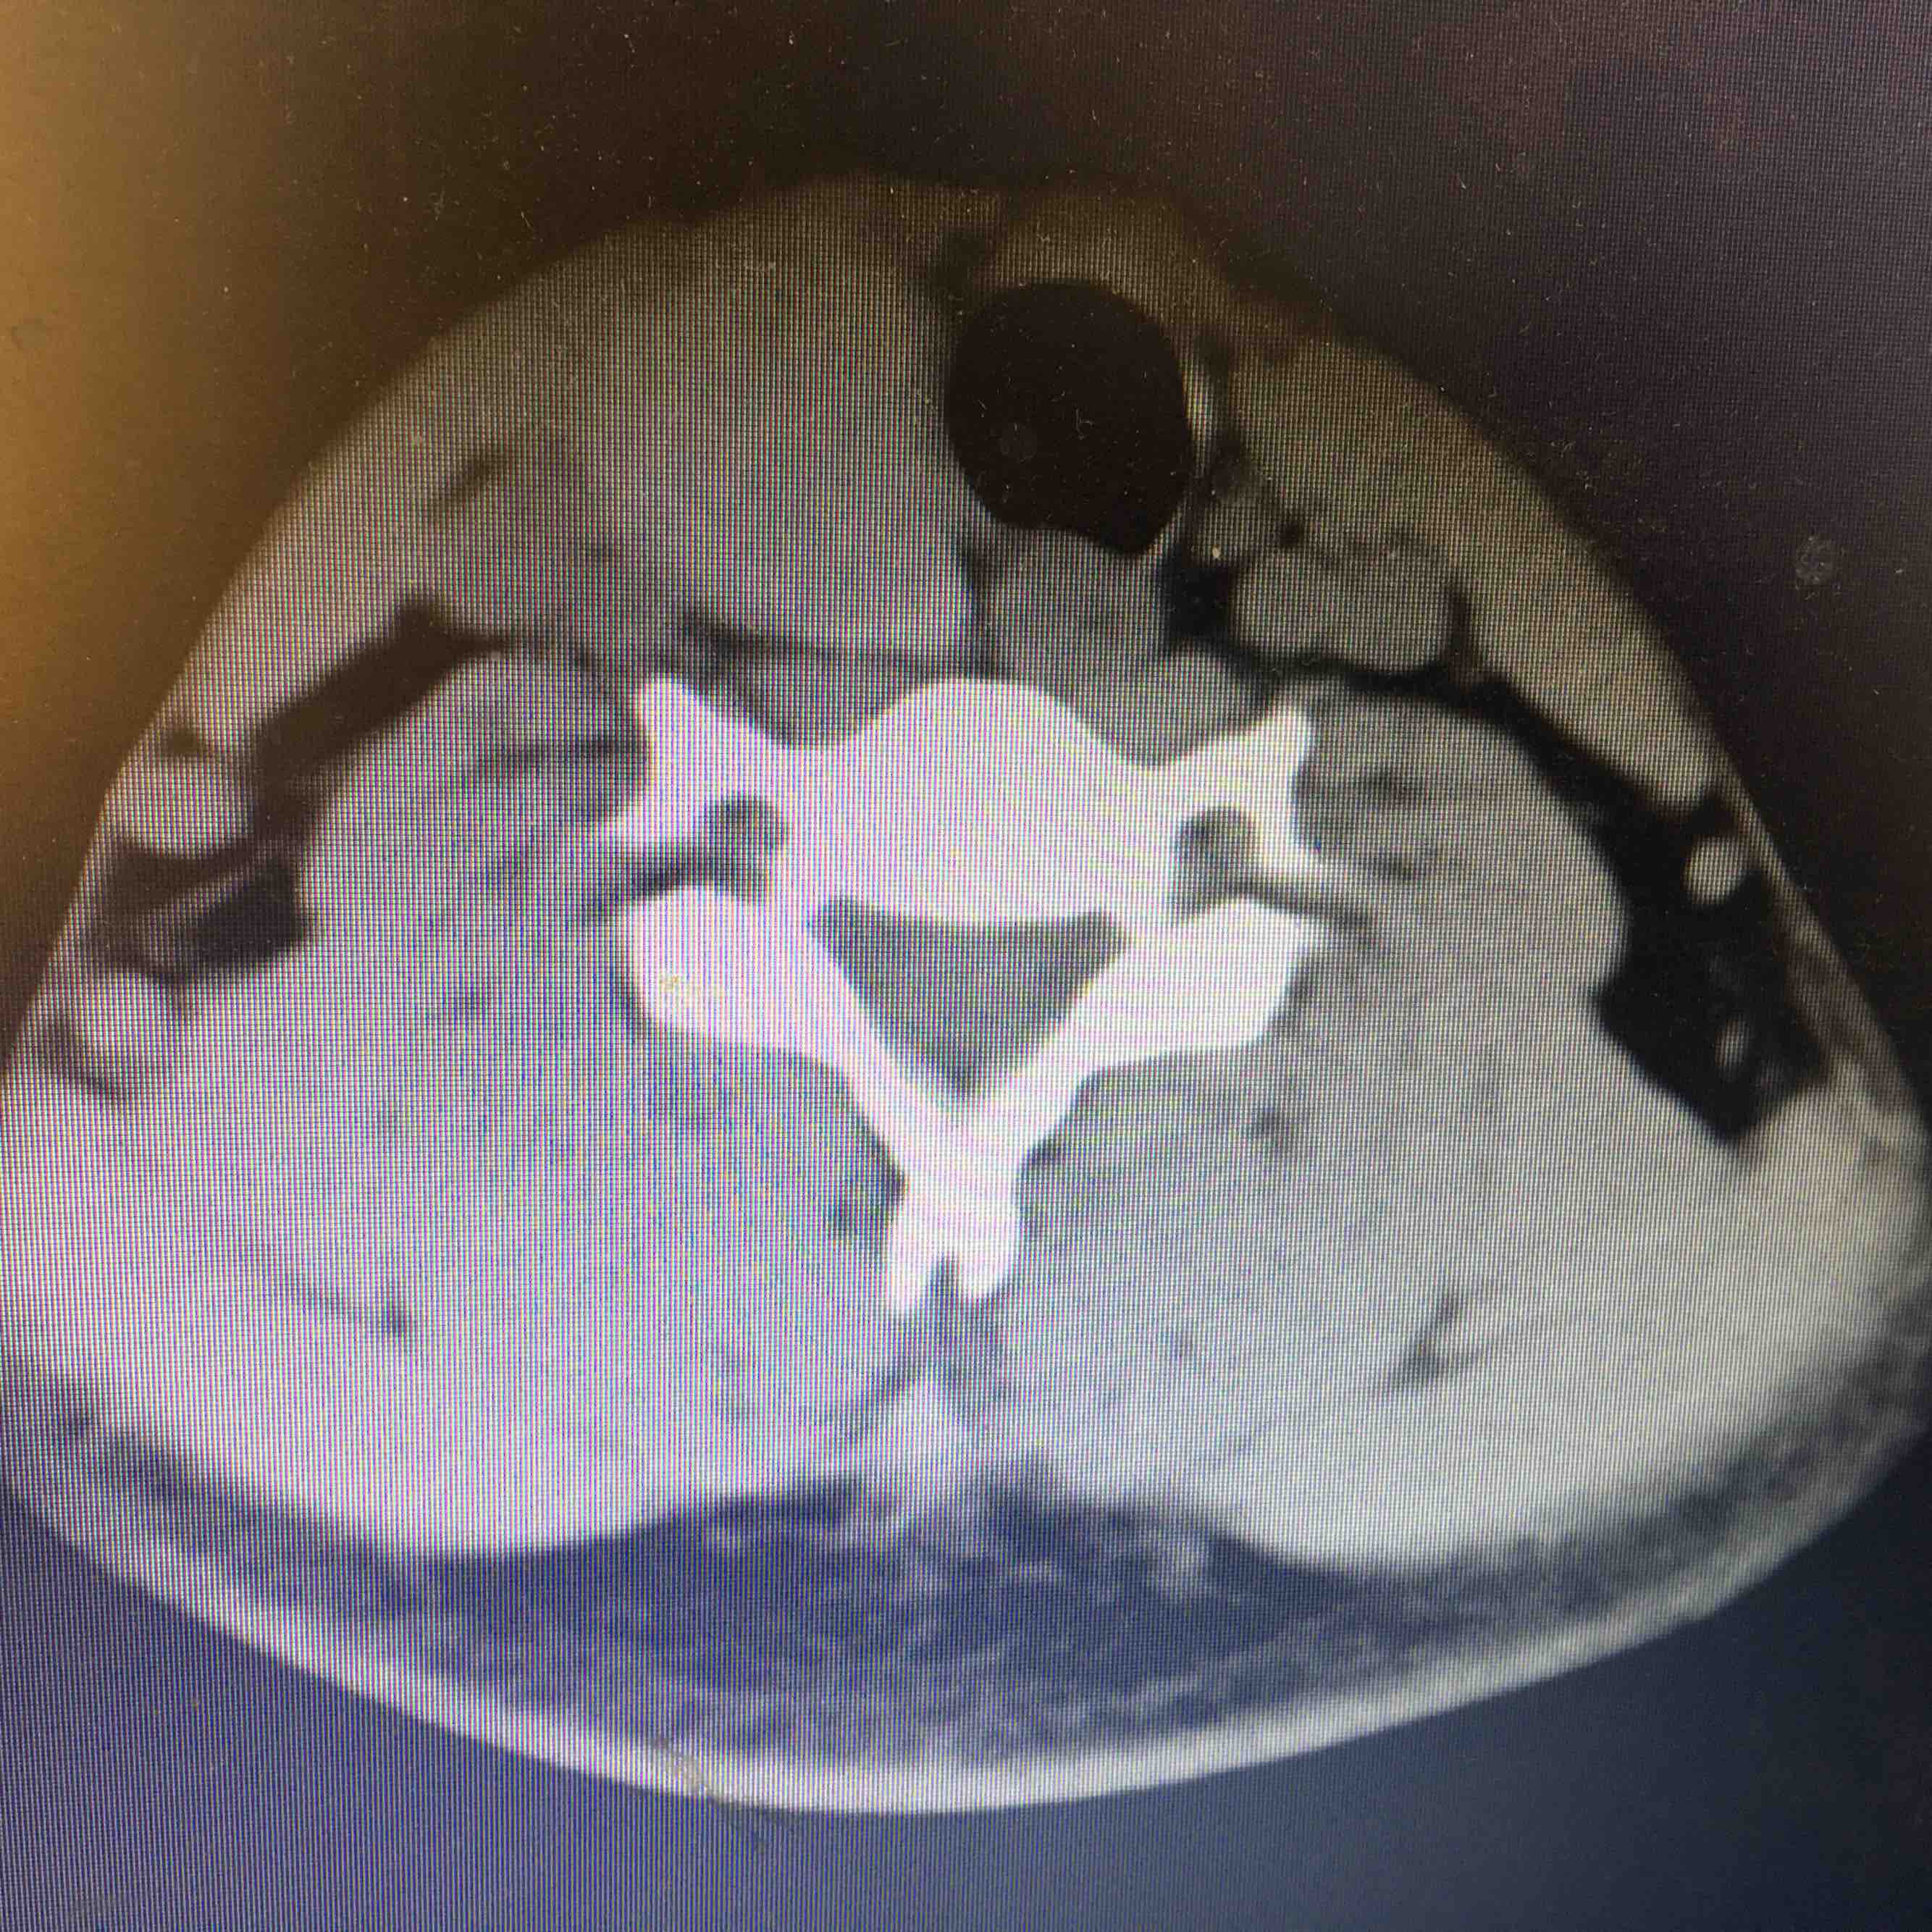

查体  颈软,气管向左侧移位,甲状腺右侧叶可触及一大小约3cm✖️3cm肿物,质韧,表面光滑,边界清晰,可随吞咽上下移动,局部压痛阴性。辅助检查  甲免五项正常。甲状腺彩超示甲状腺右侧叶囊实性病变,甲状腺左侧叶显示不出,考虑缩小。颈部CT示右侧甲状腺占位置病变,建议进一步检查,左侧及峡部甲状腺缺如,请结合临床。

诊断 甲状腺右侧叶肿物 性质待查      甲状腺左侧叶峡部缺如处理 患者要求赴上级医院进一步检查和治疗

先天性甲状腺一侧叶缺如非常少见,需要进一步完善相关检查,了解有无异位甲状腺组织。